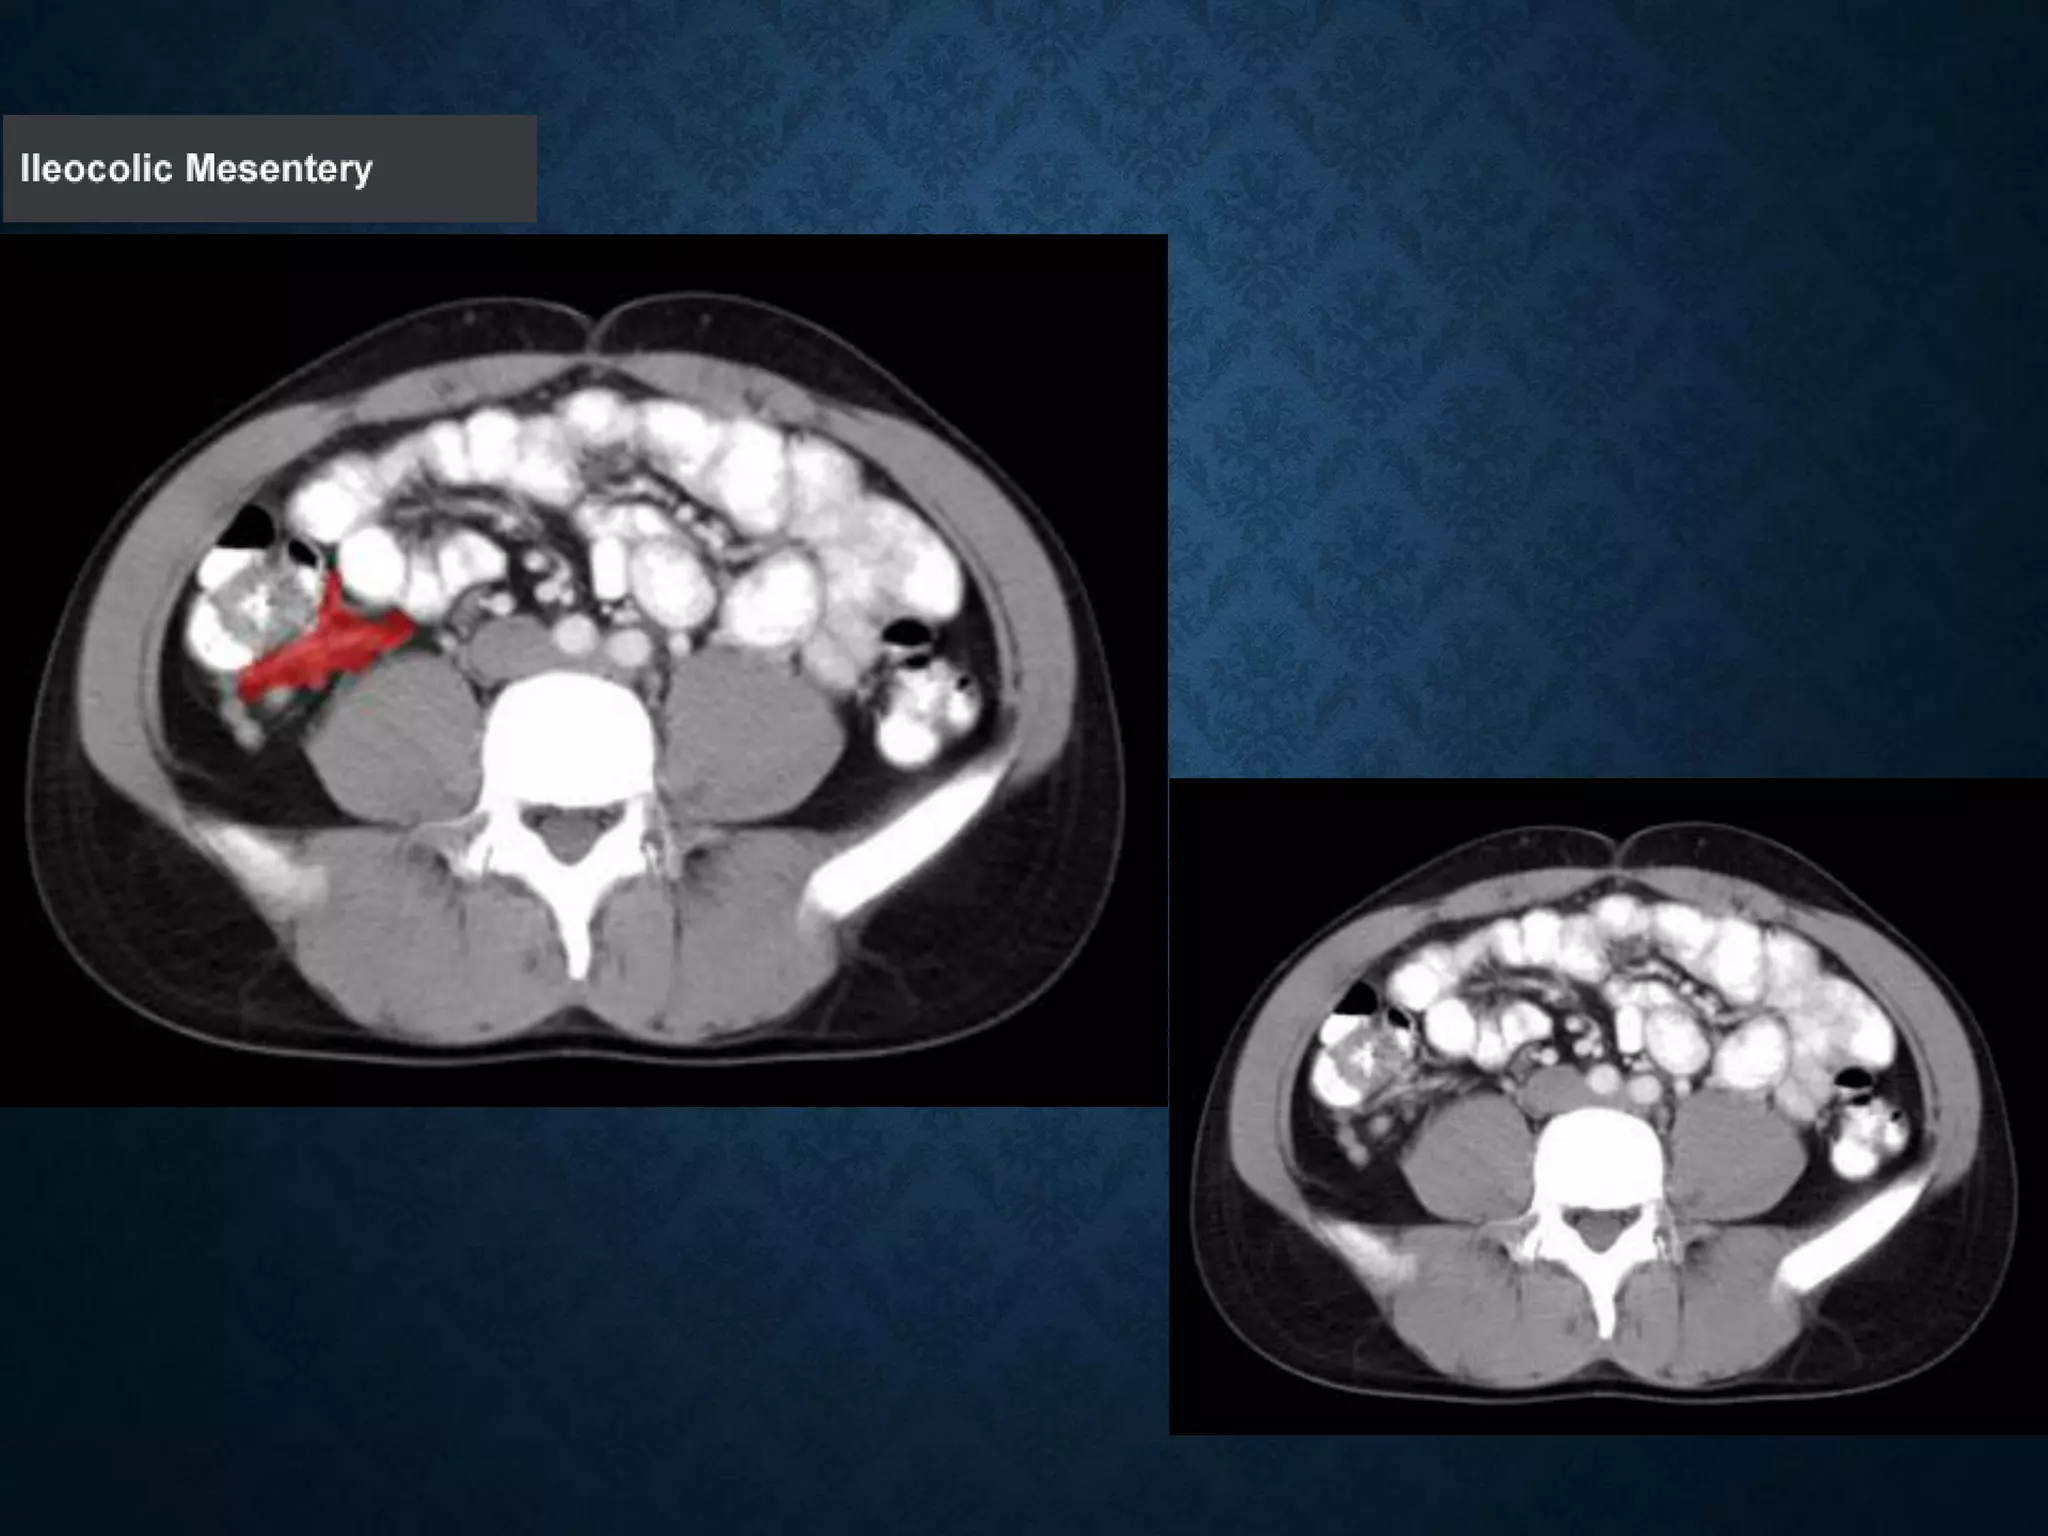

Identify the following structures in the body CT to the right. To view the location of the structure in the image click on

the label at the left and the structure will be indicated in the image. Abdominal CT scans typically begin just above

the diaphragm, so the first slice you see is of the lower chest.

Identify the followingstructures in the body CT to the right. To view the location of the structure in the image click on the label at the left and the structure will be indicated in the image. Abdominal CT scans typically begin just above the diaphragm, so the first slice you see is of the lower chest.